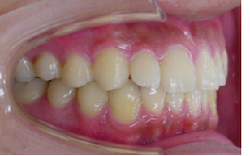

初診時

終了時

当矯正歯科医院では非抜歯で治療をしています。

治療後の後戻りが矯正では問題となりますが歯を抜かないで治療しているため、後戻りも最小限で済みます。